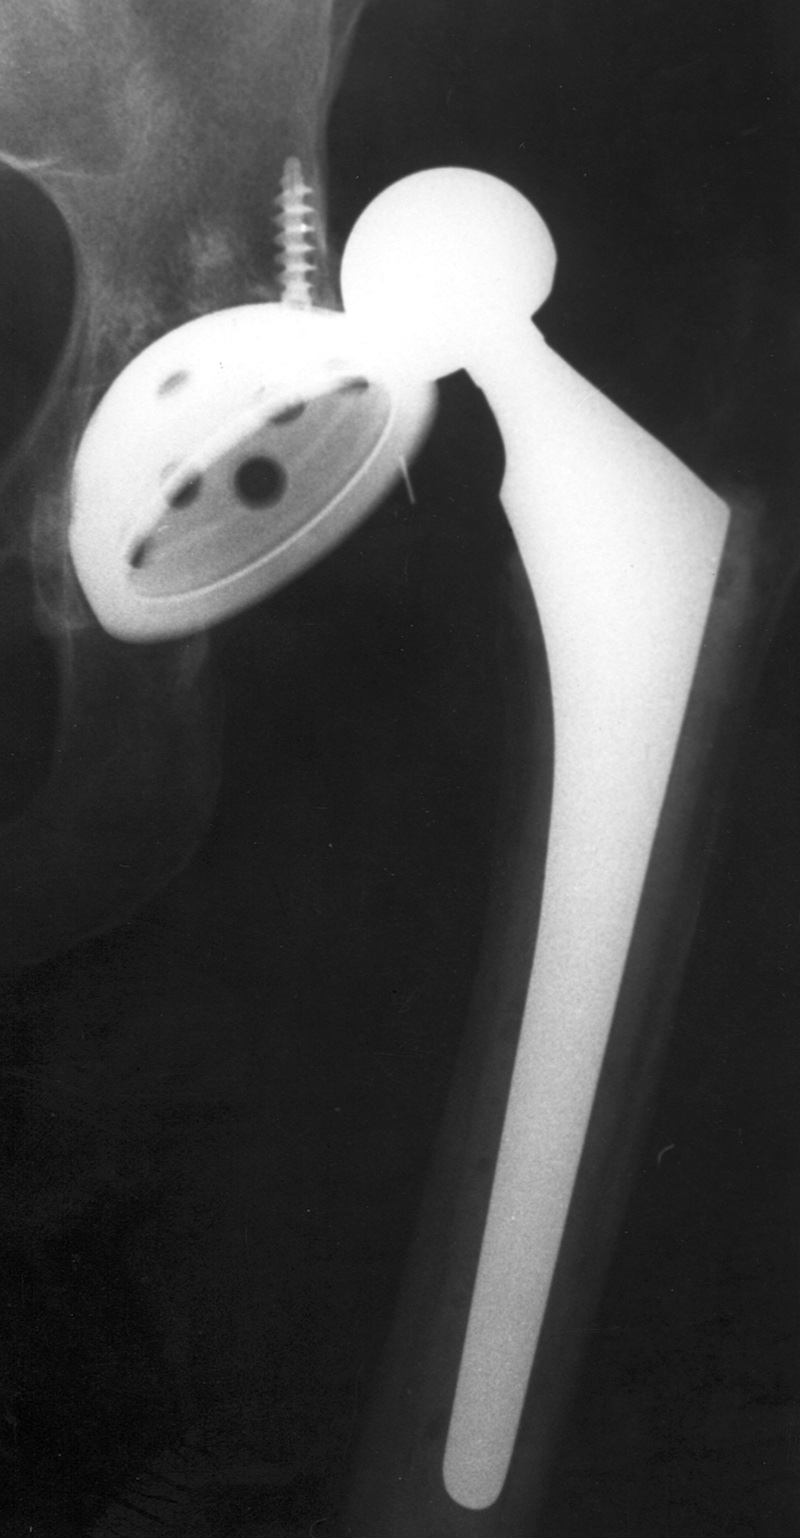

protrusio (Berquist, 1995; Benjamin, 1994). There are variations on the standard bipolar hip prosthesis with claw plates or cerclage wires used to stabilize the stem of the prosthesis (figure: bipolar hemiarthroplasty with claw plate).

| Bipolar hemiarthroplasty with claw plate and cables

| 78 year-old woman with prior bipolar hemiarthroplasty; presently treated with claw plate and cables for intertrochanteric fracture.